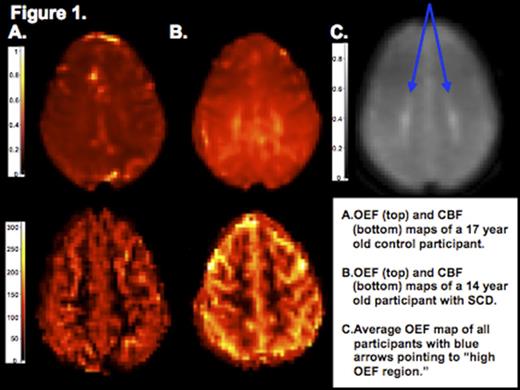

Thirty-six participants, 8 controls and 28 with SCD (26 HbSS and 2 HbSB0), ages 5-21 years, were recruited from St. Louis Children's Hospital. Participants underwent brain MRI with measurement of CBF via pseudo-continuous arterial spin labeling and OEF via a novel processing of asymmetric spin echo sequence that measures tissue deoxyhemoglobin. CBF and OEF maps were individually co-registered to corresponding T1 images with FMRIB's Linear Image Registration Tool, and gray and white matter were segmented with FMRIB's Automated Segmentation Tool. Visual inspection identified a region of high OEF within the deep white matter of the frontal and parietal lobes in the majority of subjects (figure 1 a,b). OEF maps from control and SCD participants were coregistered and averaged into a single map, and then an OEF threshold of 47.5% was applied to demarcate this "high OEF region" (figure 1c). Hemoglobin (Hb) and hematocrit were obtained in SCD participants, while these values were assumed for the controls. Arterial oxygen content (CaO2) was calculated as 1.36 x Hb x SpO2. Comparisons were made with a Mann-Whitney U test or Student's t-test. Bivariate correlations were tested with Kendall's tau b. Bonferroni correction was used in determining significance. Multivariate linear regression modeling with block entry described covariates associated with CBF.

The control and SCD cohorts did not differ in age, gender or SpO2. SCD participants demonstrated higher whole brain, gray matter and white matter CBF and OEF when compared to controls (table 1, figure 1a-b), but there was no difference in whole brain or segmented measures of CBF and OEF between SCD participants with structurally normal brain MRIs (n=16) and silent infarcts (n=12). SCD participants' OEF was higher within the "high OEF region" when compared to controls (table 1), but the regional OEF did not differ between SCD participants with structurally normal brain MRIs versus silent infarcts. Whole brain CBF negatively correlated with age (b = -0.554, p < 0.001), while whole brain OEF did not (b= 0.014, p = 0.921). Lower CaO2 correlated with higher whole brain CBF (b = -0.329, p < 0.016) and higher whole brain OEF (b = -0.587, p < 0.001). CaO2 remained a predictor (β = -0.38, p = 0.009) of CBF when controlling for age (β = -0.63, p < 0.001).

We report the first whole brain, segmented and regional analysis of oxygen metabolism, including CBF and OEF, in a pediatric SCD cohort unaffected by overt stroke. Elevation in both CBF and OEF in response to low arterial oxygen content suggests children with SCD are chronically compensating to meet the brain's metabolic demands. OEF is more elevated in children with SCD when compared to healthy controls within the "high OEF region," which coincides with previously reported locations of silent infarcts. We propose that the "high OEF region" provides a tissue signature of vulnerable, metabolically stressed brain that is at risk for future stroke.